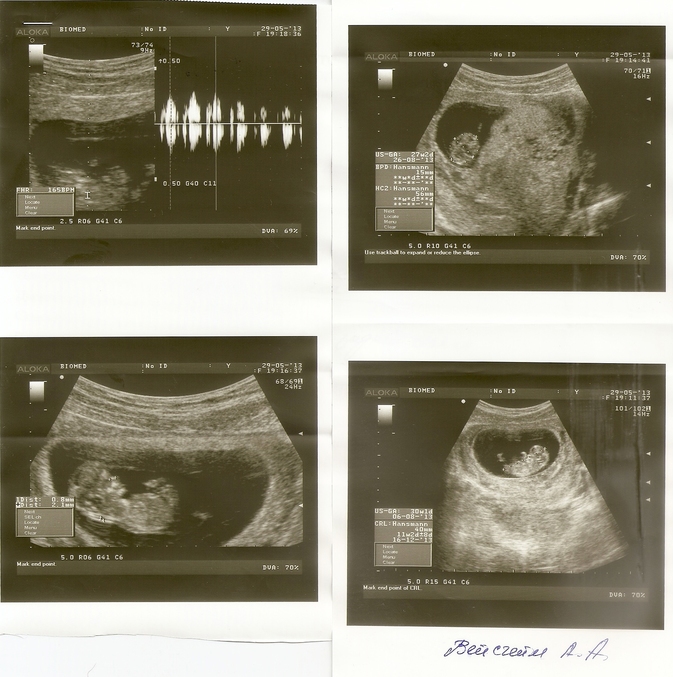

Были на Узи - помимо всех данных- которые в норме

сказали что скорее всего будет мальчик.

Срок 13 недель и 3 дня

КТР - копчико теменной размер = 66мм

ТВП - Толщина воротникового пространства = 1,2мм

НК - длинна носовой кости- 3мм

Сердцебиение 153 уд./мин.

Итак - была на узи. Наш малыш устроил трабабл - руками махали, пинались - ужасть. Врач сказала такой же активный как сын Ваш (он там по кабинету бегал и приёмной как ракета и везде лез) - говорит мальчик наверное будет